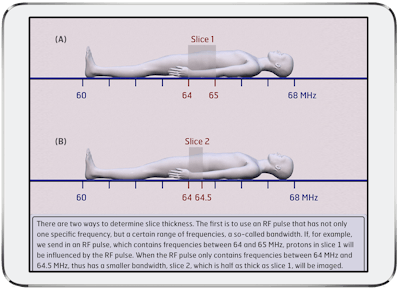

MRI Made Easy… well almost, BestApps (iOS)

The winner of the 2024 Minnies award for Best Educational Mobile App returns again as a finalist. MRI Made Easy continues to serve as a “classic introduction to MR physics, reimagined for iOS.”

MRI Made Easy… well almost is an animated app designed to serve as an introduction to MR physics.Wouter Veldhuis, MD, PhD.

MRI Made Easy… well almost is an animated app designed to serve as an introduction to MR physics.Wouter Veldhuis, MD, PhD.

The fully animated app features a searchable, “dynamic” index designed to serve as a reference for quickly looking up MR phenomena and underlying physics. It can also be read cover to cover, according to Wouter Veldhuis, MD, PhD, of the University Medical Center Utrecht in the Netherlands.

In addition, there’s also a quiz for users on their physics knowledge. All questions are answered directly and with links to the full-text background information.

MRI Made Easy is part of the doRadiology family of educational mobile apps, which also includes perennial Minnies contender Radiology Assistant 2.0.